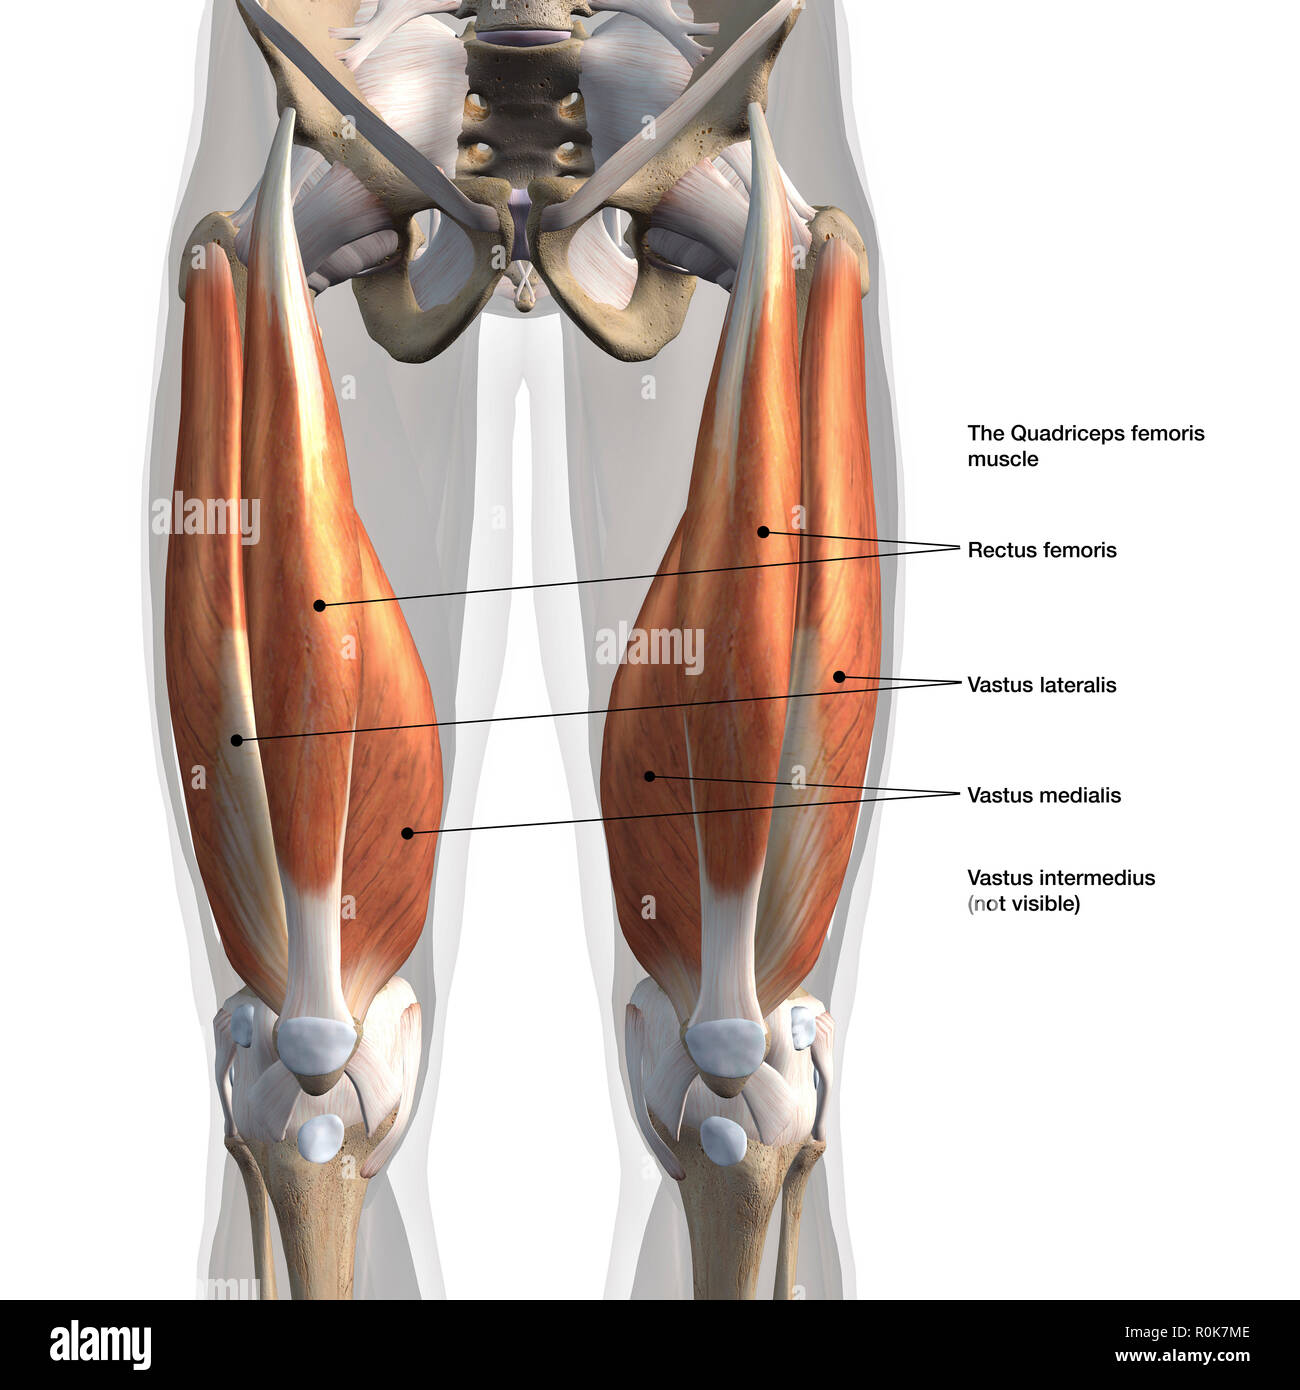

Vue antérieure des muscles quadriceps mâle avec des étiquettes. Banque D'Imageshttps://www.alamyimages.fr/image-license-details/?v=1https://www.alamyimages.fr/vue-anterieure-des-muscles-quadriceps-male-avec-des-etiquettes-image224157934.html

Vue antérieure des muscles quadriceps mâle avec des étiquettes. Banque D'Imageshttps://www.alamyimages.fr/image-license-details/?v=1https://www.alamyimages.fr/vue-anterieure-des-muscles-quadriceps-male-avec-des-etiquettes-image224157934.htmlRFR0K7ME–Vue antérieure des muscles quadriceps mâle avec des étiquettes.